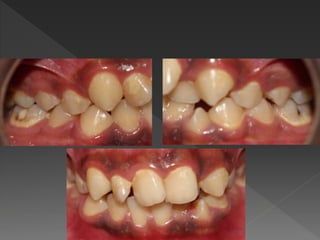

 U-shaped lower arch

 Anterior segment:

› crowding in anterior

segment with impacted

lower right 3 and rotated

lower left 3.

› Lower midline shift to the

right 3mm.

 Buccal segment:

Rotated lower 4 and 5

bilaterally.

 U-shaped arch.

 Instanding upper

left 2.

 Rotated upper

right 1,2, and 3.

And left 1 and 3.

 Midline is shifted

to the left 3 mm.

 Class II div 1 incisor relationship.

 Upper midline shifted to the left 3 mm.

 Lower midline shifted to right 3 mm

 Overjet = 5 mm

 Overbite = 20% incomplete.

 Molar relationship: L: Class I R: Class I

 Canine relationship: L: ¼ unit Class III